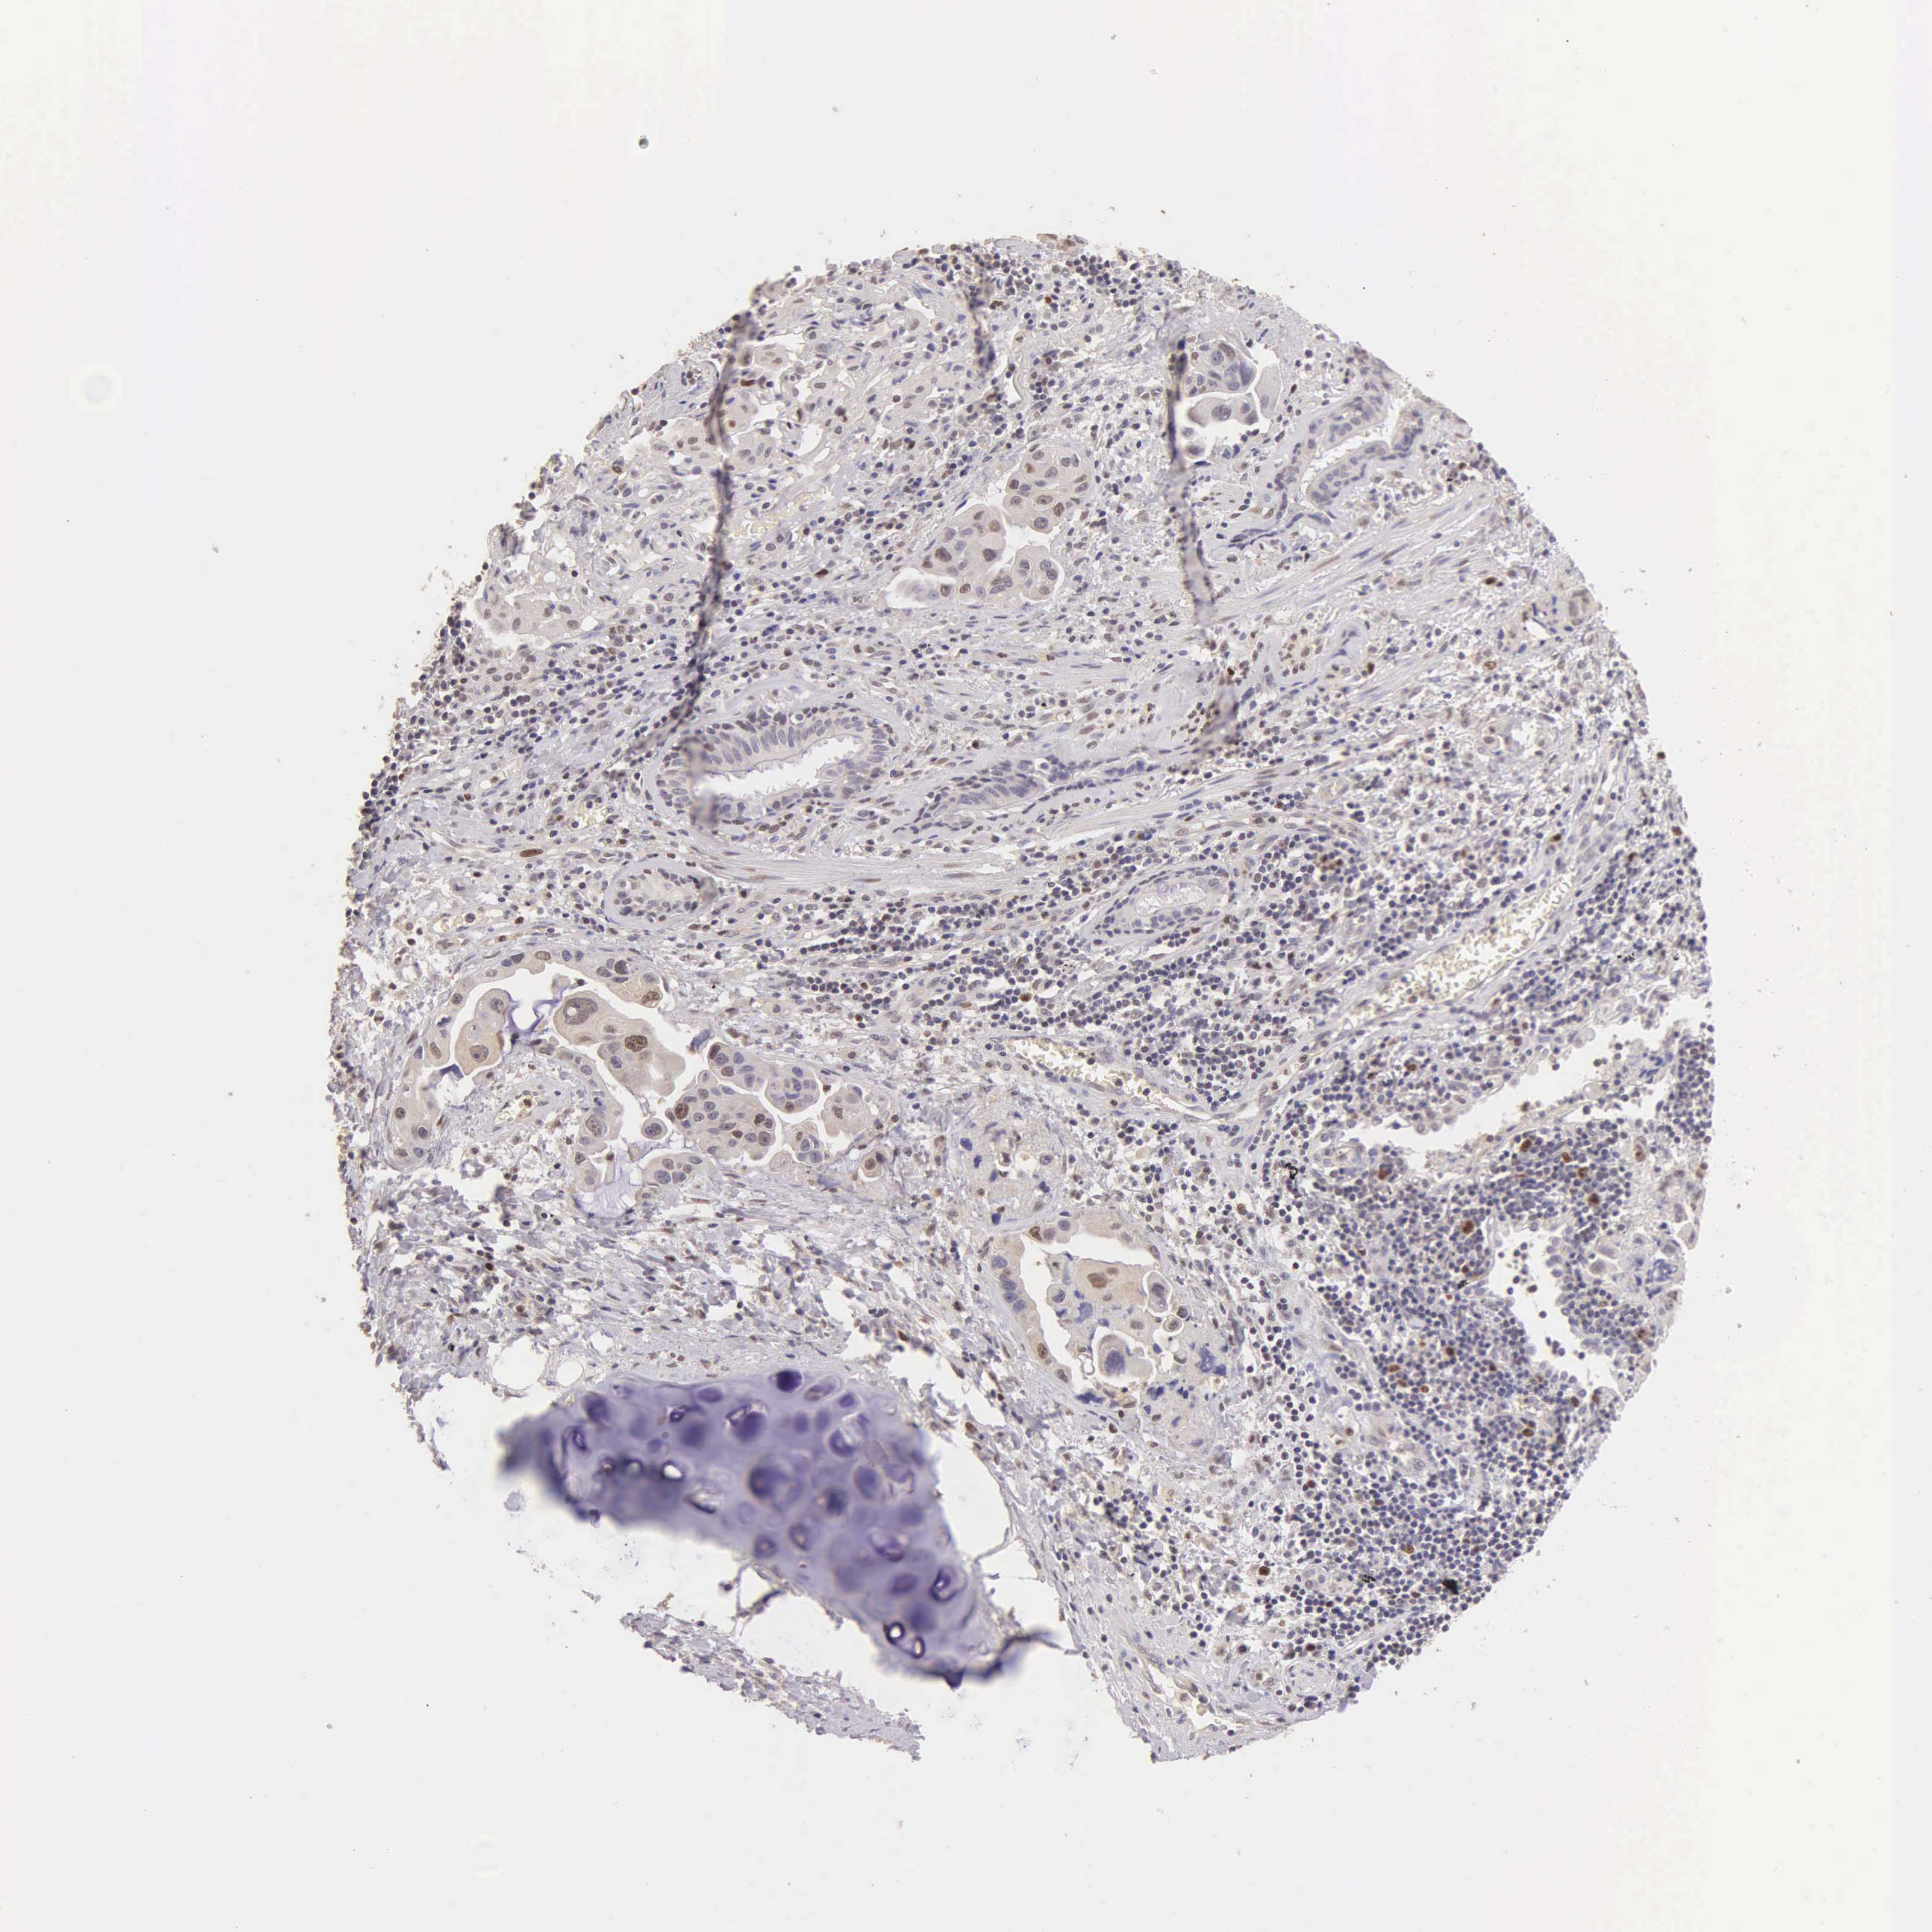

CANCER LUNG CANCER Show tissue menu

LUAD TCGA LUAD VALIDATION LUSC TCGA LUSC VALIDATION PROTEIN LUAD CPTAC PROTEIN LUSC CPTAC PROTEIN EXPRESSION